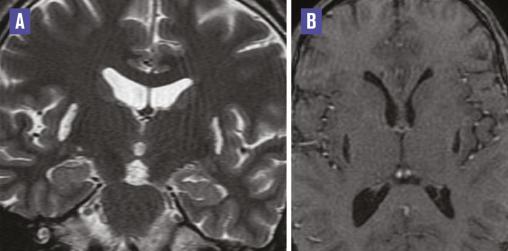

Cet homme de 36 ans, alcoolique chronique, était admis au service d’ophtalmologie pour l’exploration d’une cécité bilatérale. L’imagerie par résonance magnétique (IRM) orbito-encéphalique, demandée dans le cadre du bilan causal, montrait une atteinte putaminale bilatérale et symétrique de signal liquidien ; hyperintense en T2 (fig. 1A ), hypo-intense en T1 et Flair, sans restriction de la diffusion (fig. 2 ) ni rehaussement sur les séquences injectées (fig. 1B ) en rapport avec une nécrose de liquéfaction de type pseudokystique putaminal. Les voies optiques et la substance blanche sous-corticale étaient sans anomalie. Le diagnostic d’une intoxication au méthanol était confirmé par un taux sanguin élevé de méthanol.